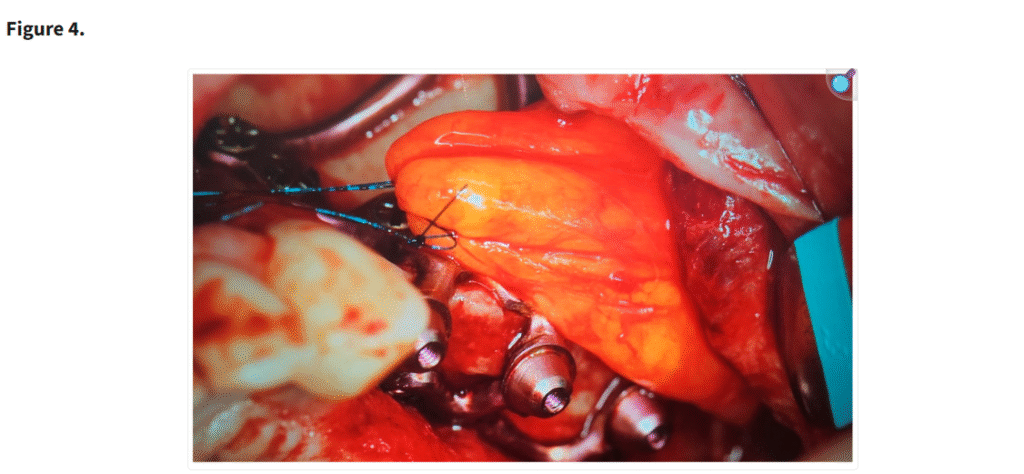

十分な視野が得られた段階で、患者の上顎解剖に正確に適合するように設計されたカスタムサブ骨膜下インプラントを歯槽堤上に配置した(Figure 1)。一部の症例では、歯槽堤が狭く高い場合にテンプレートを用いて骨を削除した(Figure 2・Figure 3)。手術中に頬脂肪体が脱出した場合には、MaIインプラント®(Integra Implants®, ロッジ、ポーランド)の前庭側表面に縫合した(Figure 4)。また一部の症例では、オトガイ部や外斜線から骨片を採取し、MaIインプラントの枝を覆う目的で使用した(Figure 5)。

MaI インプラント®(Integra Implants®, ロッツ〔ポーランド〕)上に覆われた頬脂肪体。脂肪体は吸収性縫合糸を用いて縫合することができ、その場合は骨膜に固定される。あるいは非吸収性縫合糸を用いて縫合することも可能であるが、この場合は結紮部を歯肉の上に残し、最低10日後に抜糸できるようにしなければならない